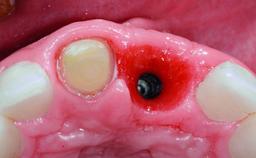

Replacement of a Compromised Upper Right Central Incisor: Hard- and Soft-tissue Augmentation, Late Placement of an RC Bone Level Implant

A 36-year-old male patient with a compromised maxillary central incisor was referred by his general dentist for consultation. The patient’s chief complaints were the gradual debonding of a temporary crown on the right central incisor and unsatisfactory esthetics due to an increasing diastema between the right central and lateral incisors. The patient reported a traumatic event some years previously, when a crown had been placed after root-canal treatment. The referring dentist wanted to provide a new crown restoration, but was concerned about the condition of the residual root. Anamnesis was negative for any other dental or periodontal pathology in the remaining dentition. The patient reported taking no medications: He was a smoker (10 to 15 cigs/day) and had realistic esthetic expectations.

Type of Implants Two-Piece

Attachment Two-Piece

Bone Augmentation Horizontal|Simultaneous|Staged

Augmentation Materials Xenogenous|Membrane

Bone Volume Deficient horizontally, requiring prior grafting